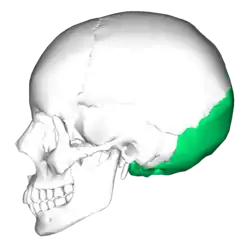

Kranium (Occipitalknogle nederst til højre). | |

Placering af occipitalknogle (vist med grønt) | |